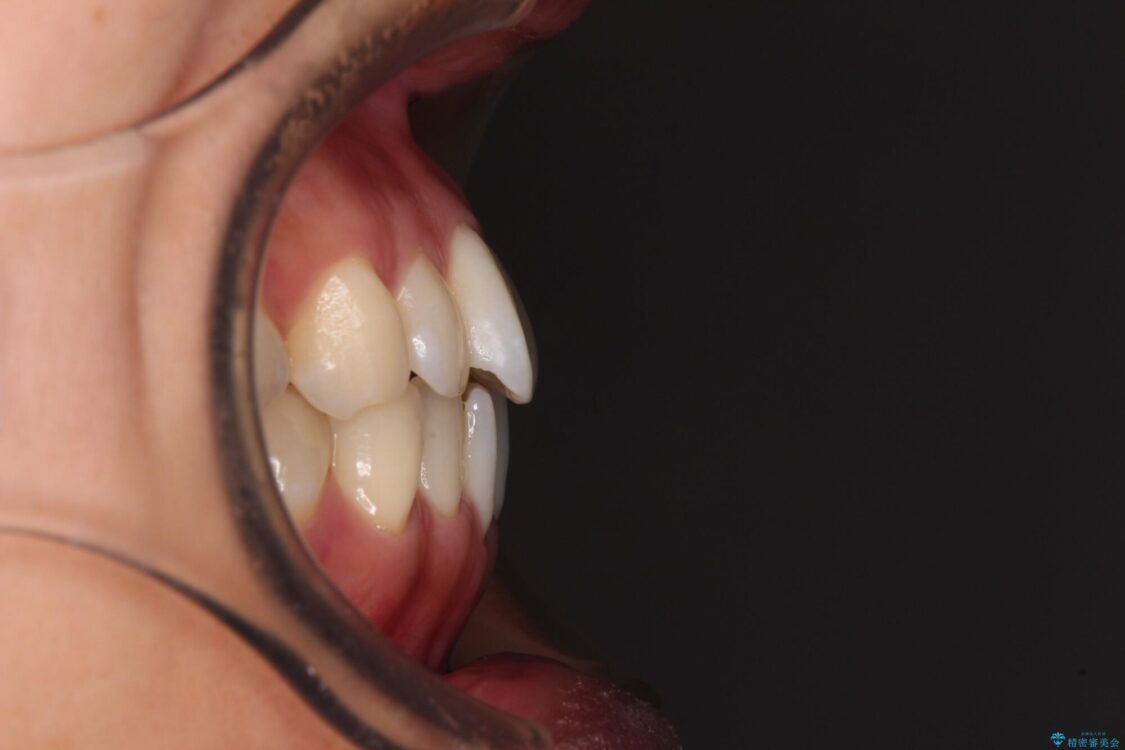

上顎前歯が捻れて前方に飛び出しており、下顎前歯もそれに沿うようにデコボコとなっていました。

IPR(歯と歯の間を削る処置)によりスペースを獲得して上下顎前歯のデコボコを改善し、飛び出している前歯が引っ込むように設定し、インビザラインにて矯正治療を行うこととしました。

治療途中

• 【モニター】前歯のデコボコをインビザラインで改善 治療途中画像